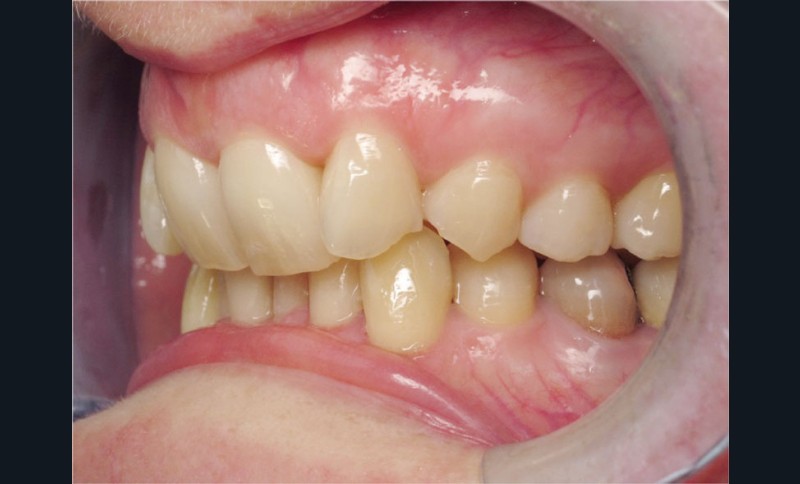

Cas n° 2

Nous lui avons donc proposé un traitement d’alignement avec maintien des 14 et 24 en position de 13 et 23 et optimisation du torque pour favoriser un développement des arcades et chercher à améliorer le sourire et le soutien labial.

La patiente donne son accord pour un appareillage Damon Insignia métal qui permet une individualisation complète des brackets dans les 3 sens de l’espace.

Un appareillage Damon métal a été mis en place, réalisé à partir d’un set up numérique Insignia pour obtenir un contrôle précis des torques et de la forme d’arcade et réduire le temps de finition grâce à un collage indirect très précis.

De larges surélévations postérieures étalées ont été mises en place et la patiente a porté des élastiques précoces suivant les principes de la technique Damon. Les 14 et 24 rempliront le rôle des 13 et 23.

L’objectif, en utilisant la technique Insignia est de réduire le temps de traitement de 28 à 18 mois avec 12 rendez-vous (fig. 5 à 14).